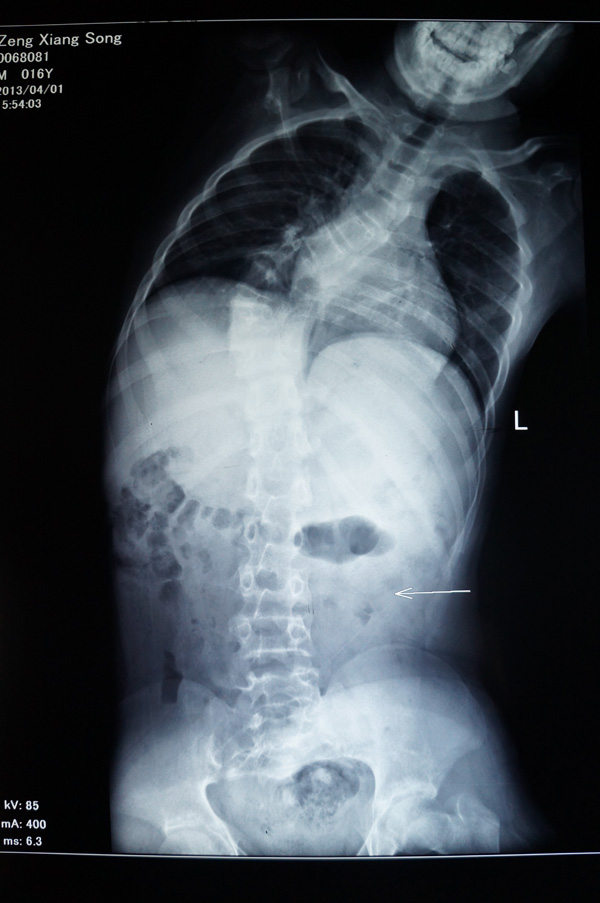

瑞康医院骨脊柱二区的医生给小松做了详细的身体检查,发现他的胸5-腰1椎体节段明显向右侧侧弯,呈小“S”形状,胸5-腰1棘突及棘突两旁无明显压痛及叩击痛,右侧竖脊肌肌张力紧张,左侧正常,站立姿势时测量左侧肩比右侧肩高约2cm。同时进行并足前屈弯腰试验时,发现小松的右侧肩胛骨明显高于左侧,出现“剃刀背”畸形,脊柱左右侧弯柔软性差,Cobb角65°[i],胸腰椎MRI平扫检查确诊:脊椎侧弯畸形。

小松术前的X光片